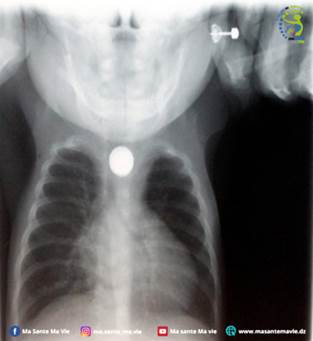

Le diagnostic : une pile bouton logée dans l’œsophage

L’imagerie révèle une opacité circulaire métallique au niveau de l’œsophage, indiquant la présence d’une pile bouton. L’enfant a immédiatement été orienté vers un service de chirurgie pédiatrique. Un scanner thoracique montre une nécrose œsophagienne avec un trou (perforation), signalant une complication grave.